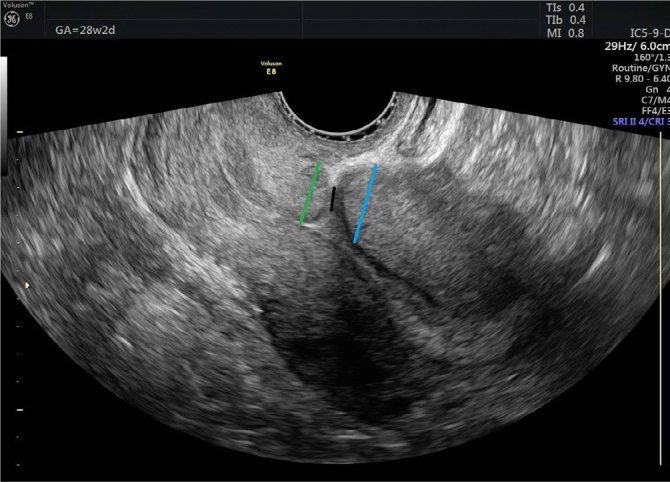

Material and methods: This prospective study included pregnant women diagnosed with diabetes mellitus and healthy control pregnant women. The study group was divided into active labor and pre-active labor based on cervical dilatation, and the diabetic group was categorized into gestational diabetes and preexisting diabetes mellitus. Vaginal ultrasound was performed in the entire study group at six months postpartum, and the location of the cesarean scar was evaluated.

Abstract Image